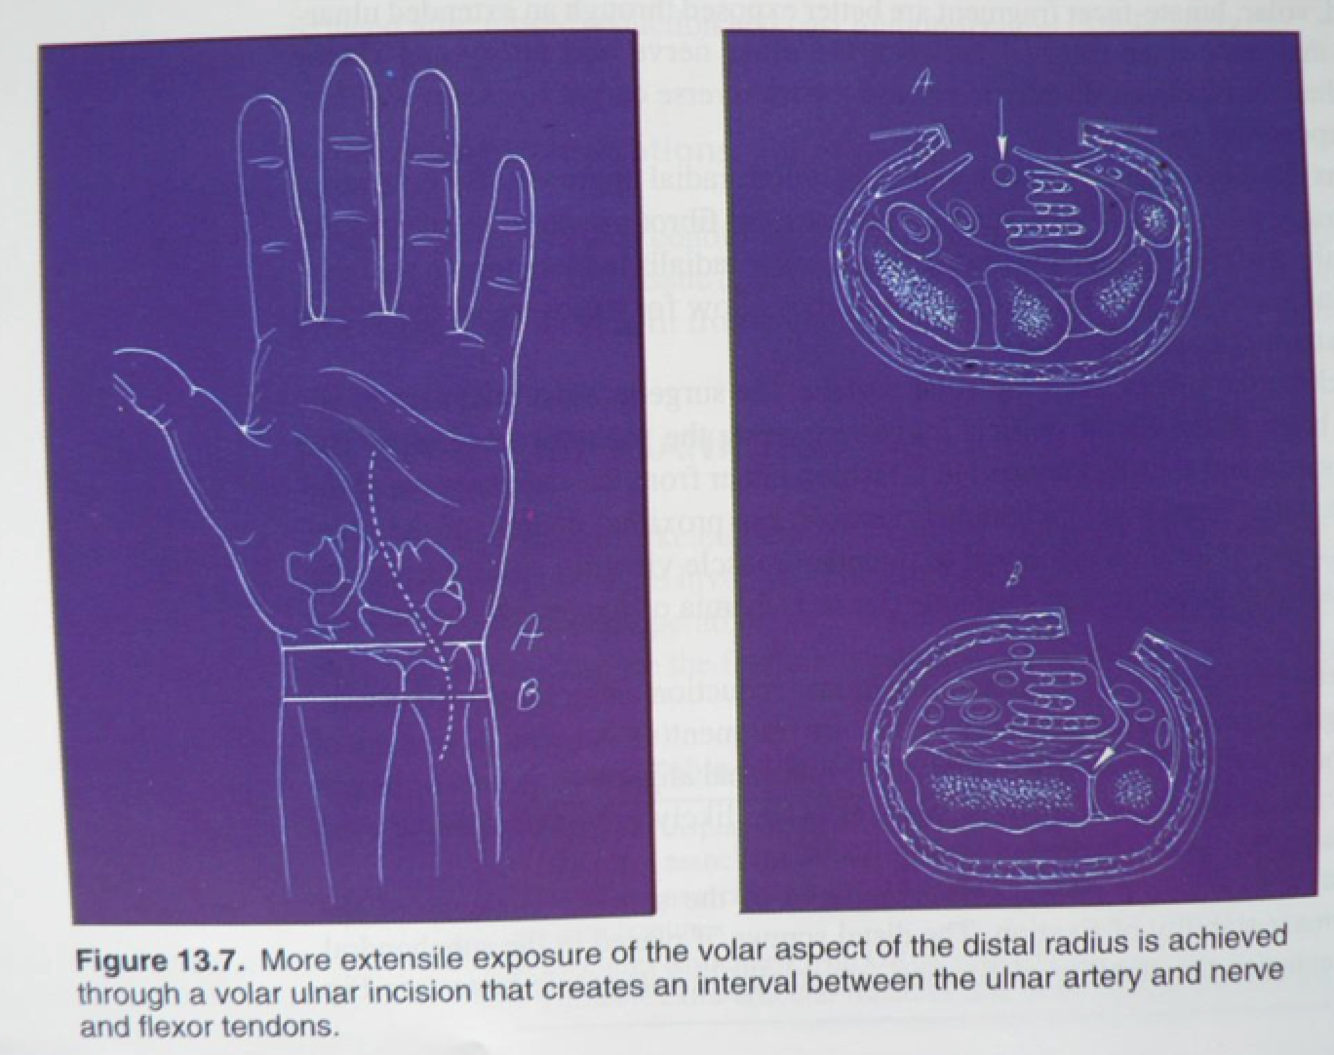

Volar Ulnar Approach at the Wrist

Interval: Flexor Tendons [(FDS) - Median N.)] & Ulnar A.

Approach: Develop interval between FDS and FCU. Work proximally to identify ulnar a. and ulnar n. Develop interval between ulnar a. and flexor tendons. Identify PQ, lift PQ radially to reveal ulnar aspect of distal radius. Can follow ulnar n. and relase guyons canal, can release carpal tunnel through this approach as well.

Dangers: Ulnar A. Ulnar N.